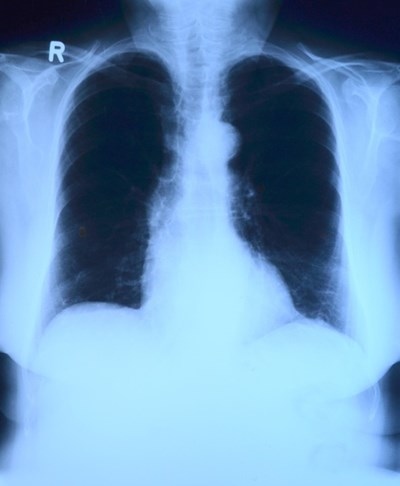

Учени откриха изненадваща реакция на белодробните клетки, заразени с вируса SARS-CoV-2, която може да обясни защо лечението на инфекцията Ковид-19 е толкова трудно, съобщи електронното издание "Медикъл Експрес".

Изненадващо, изследването на международния екип установило, че този имунен отговор се задейства в алвеолите, каза Каземиян.

"Това беше напълно неочаквано за нас, защото не сме и мислили за активирането на тази система в клетките или поне не в белодробните клетки. Обикновено мислим за черния дроб като за източник на системата на комплемента", поясни той.